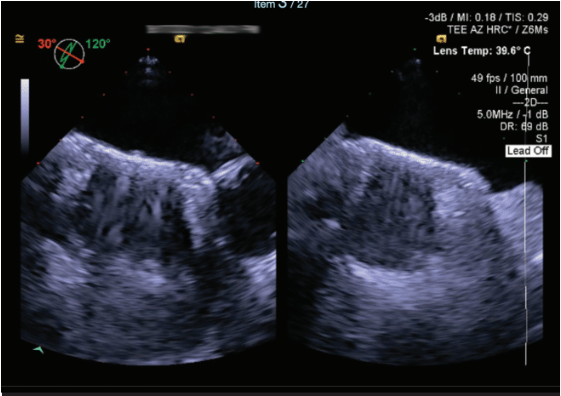

However, a few years after the ASD closure, he experienced a recurrence of AF, requiring DCCVs and the use of antiarrhythmic medications. By 2021, clinical follow-up revealed both AF and AAFL. At that time, all antiarrhythmic treatment options had been exhausted, which either failed or were not tolerated by the patient. Consequently, a repeat ablation was considered. A recent TEE showed the ASD occluder device with a very small posterior superior rim, measuring approximately 1-2 mm.

Due to the complexity of the transseptal puncture, the decision was made to have 2 operators perform the case. To ensure the most accurate visualization of the ASD occluder and the target puncture site, 4-dimensional TEE was utilized as a guide.

TEE can be a superior tool in guiding transseptal puncture, particularly in complex AF cases, where anatomical challenges such as a prior ASD or patent foramen ovale (PFO) closure device are present. TEE provides real-time, high-resolution imaging that enhances the precision of catheter placement during transseptal puncture, reducing the risk of complications associated with inadvertent puncture of adjacent structures. In patients with prior large ASD or PFO devices, where the anatomy of the interatrial septum may be significantly altered, the ability of TEE to clearly delineate the septum and device margins is invaluable, ensuring that the puncture is performed safely and accurately. This utility makes intraprocedural TEE an essential modality in the management of such high-risk cases, optimizing outcomes and minimizing procedural risks. Although we frequently utilize ICE during AF ablations, our operators prefer the utility of TEE when encountering challenging transseptal punctures such as this case. The limitations of obtaining consistent access to intraprocedural TEE given the scarcity of cardiac anesthesia coverage is an unfortunate reality; however, we specifically request such assistance and plan for this coverage when facing complex transseptal puncture cases.